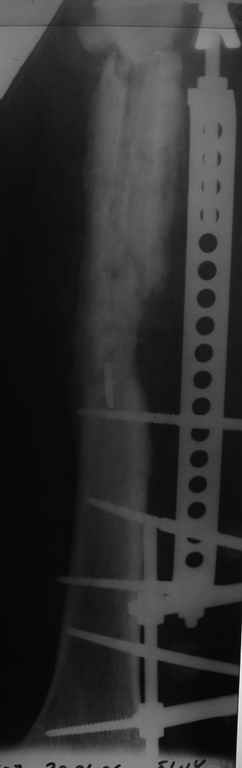

Больной 40лет, поступил 08.06.05г. с закр. оскольчатым переломом бедренной кости в с/3 и в/3 со смещ., 10.06.05г. выполнен остеосинтез LCP

,ч/з 3нед. после операции вскрыта нагноившаяся гематома, промывная система 1нед., через 3-и месяца пластина удалена в связи с инфекцией, секвестрэктомия, ЧКДО. АВФ 8мес.,периодически абсцедирование мягких тканей, санирующие операции, в настоящее время вскрыт абсцесс в с/3 бедра, м/ткани в обл. стержней инфицированы, полость абсцесса сообщается с проксим. и частью дист. стержнейдальнейшая тактика?